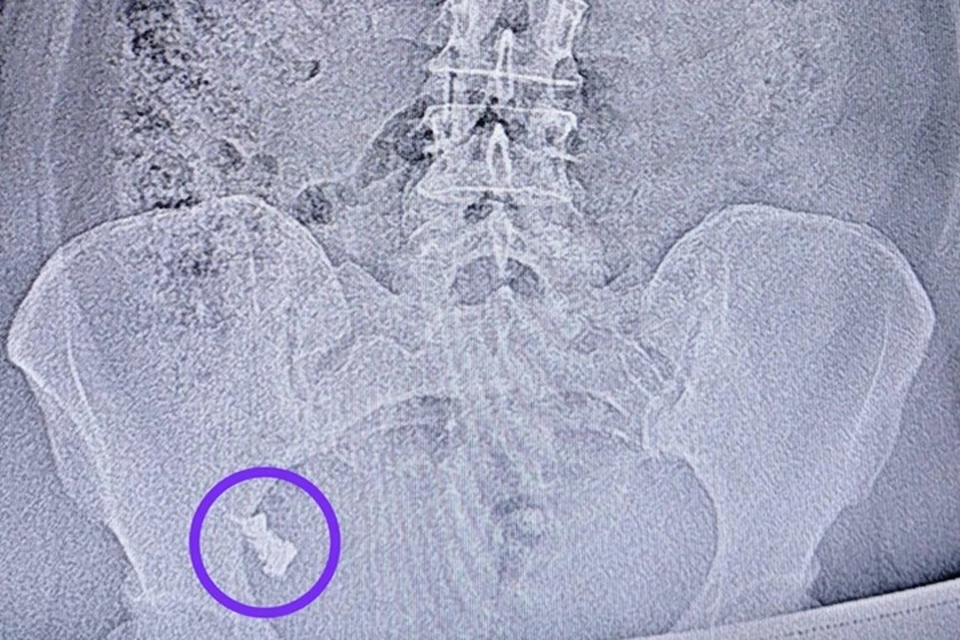

В Республиканской клинической больнице Татарстана провели уникальную операцию по извлечению зубного протеза из кишечника 50-летней жительницы Казани. Женщина случайно проглотила конструкцию, но в течение недели отказывалась от медицинской помощи, надеясь, что инородное тело выйдет естественным путем.

Ситуация осложнилась, когда протез застрял в области перехода тонкой кишки в толстую. Врач-эндоскопист Наиль Исхаков провел колоноскопию под контролем анестезиолога-реаниматолога Елены Чуенковой. Благодаря анестезии процедура прошла безболезненно для пациентки, сообщает пресс-служба РКБ.